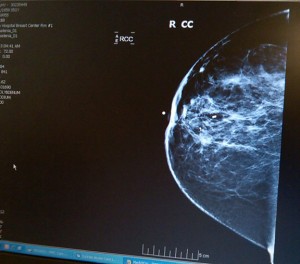

Behold, the enemy

“Those are my images, aren’t they?” I asked the radiologist in earshot of my spa-mate. I suspect that most doctors would have politely but firmly asked me to return to the waiting area.

The radiologist‘s response was remarkable. “Would you like to meet your enemy?” she asked.

Tightening the belt of my robe I said, “Yes!”

Dr. Danon asked everyone else to leave and invited me in. She began explaining the complicated topography of my images. I felt empowered and smiled through a stream of tears. Now I knew my enemy. I was the last patient to be seen that day. The kindness of the radiologist stayed with me that night.